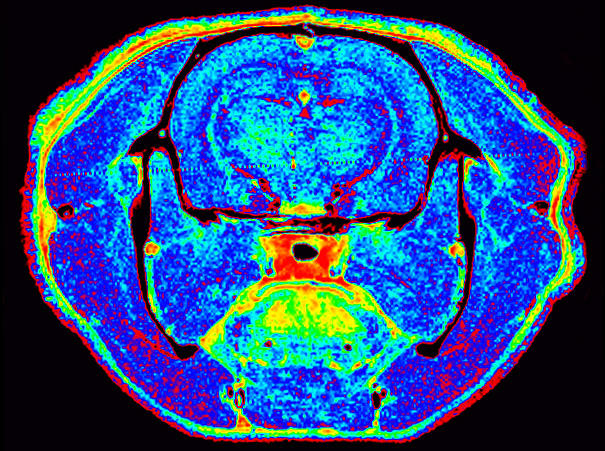

Brain

Photo:

MIC